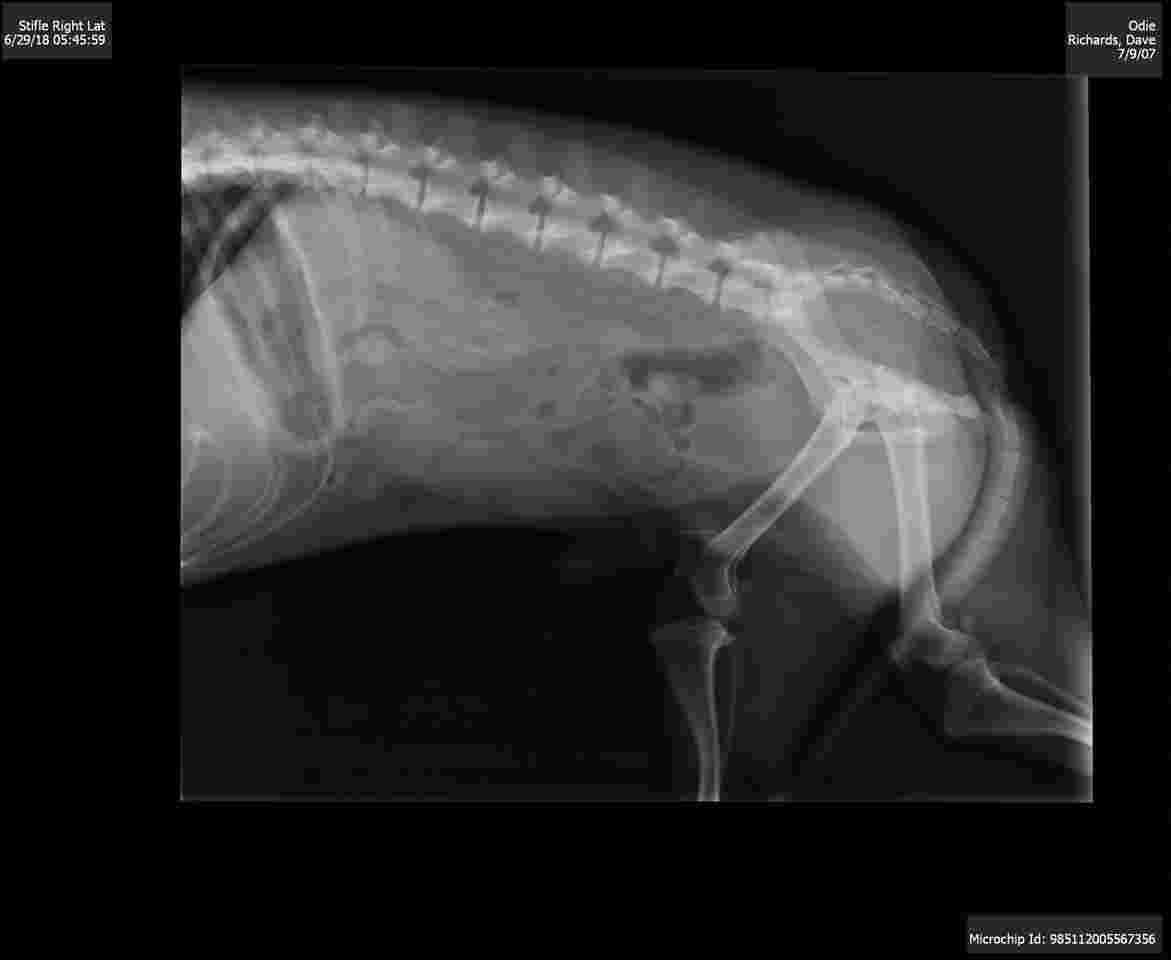

My 10 yr old chiweenie won't barely eat or drink. Tiny poops. The last vet last week said it was congestive heart failure so we have him on meds every 12 hours. He has not improved. My husband keeps contacting another vet to get him in but they aren't getting back to him. I have the two xrays they took.

Hello and welcome to Petco Pet Education Center, formerly Petcoach. I am sorry that Odie isn't feeling well. The heart on the x-rays is very big, so treatment for the heart disease is a good idea. One of the medications given typically with heart disease is a drug called Furosemide, and this usually makes them drink and pee a lot. Other medications for heart disease including Benazepril (Fortekor) and Pimobendan (Vetmedin). Benazepril can be hard on the kidneys so follow up bloodwork is recommended. If Odie is not improving with the medications he might need higher doses. Also, if he isn't eating and drinking, I would be concerned about another disease process going on, and would recommend bloodwork. You can always try a 24 hour emergency center if you can't get into your local vet for a consult. I hope he feels better soon. I wouldn't change any medications you are giving now without talking to a vet first, and it sounds like Odie needs to be seen soon. Best of luck with Odie.